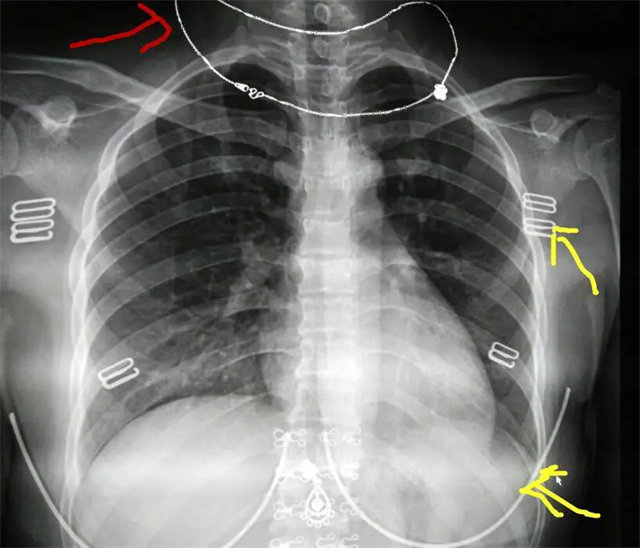

缺陷:雙側(cè)胸鎖關(guān)節(jié)不對稱,且有手機(jī)顯影。

解決:去除手機(jī)后,使患者左側(cè)緊貼成像件曝光。